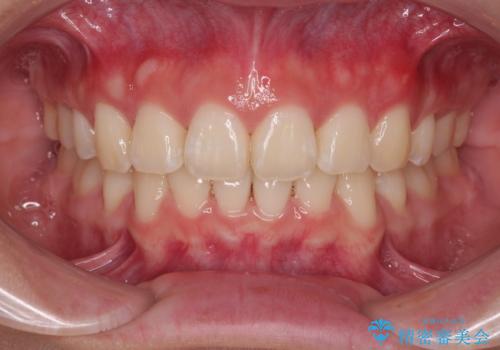

目立つ八重歯を非抜歯矯正で整える 目立たないワイヤー矯正

担当医 藤巻太一朗